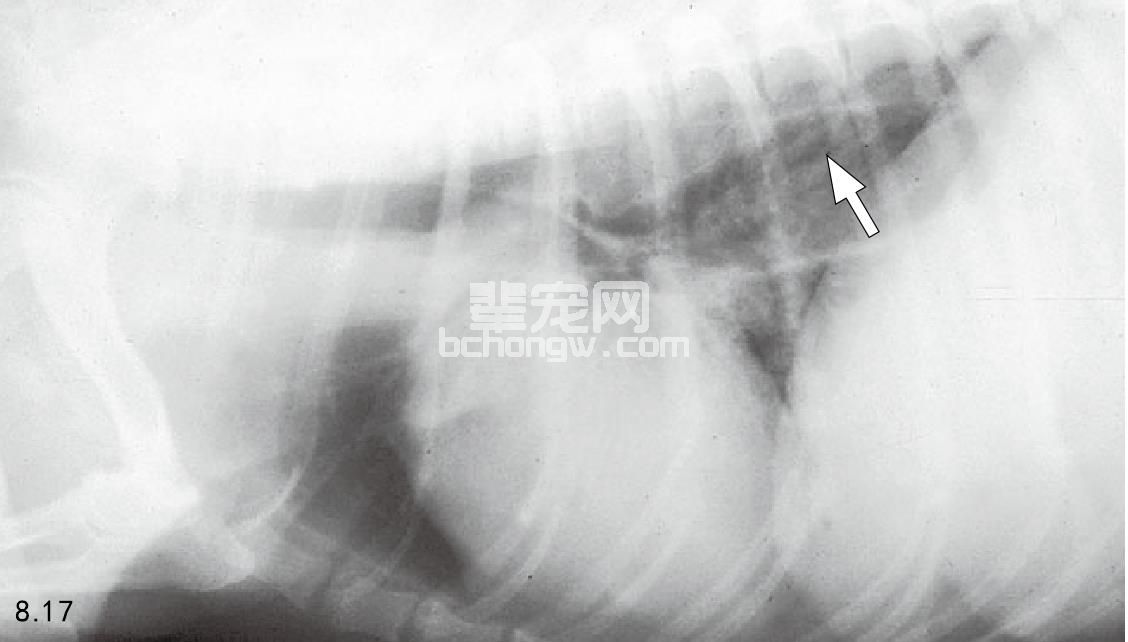

图8.17和图8.18 患重症肌无力3个月的6岁雌性腊肠犬的侧面胸片可见有巨食管(箭头所指),并最终导致吸入性肺炎。

临床症状 临床症状以运动后肌无力与感觉麻痹为特征,尤其以后肢最严重。休息几分钟后会恢复,但进一 步运动后会加剧症状(图8.14~图8.16)。许多重症肌无力的动物有巨食管、食物回流现象,有时会导致吸入性 肺炎(图8.17和图8.18),且有声音改变现象(高音)。后天获得性重症肌无力症状的严重程度不同; 某些病例 未见四肢无力症状。那些局部性的重症肌无力有面部肌无力、喉部肌无力与咽部肌无力,有或者没有巨食管。 某些犬在发作的数天到数月内会有自动缓解减轻。